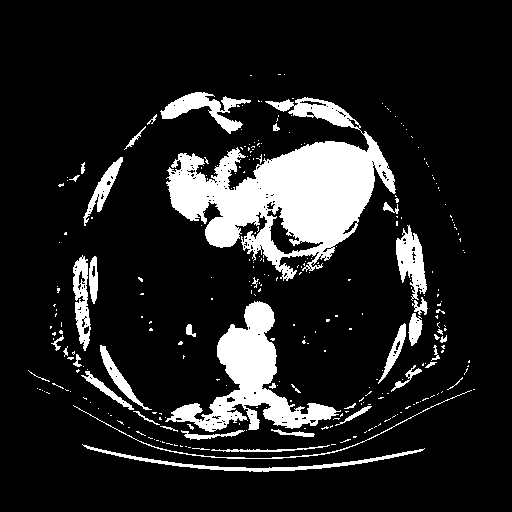

Original NATIVE CT scan (input)

Full window (WL 1023.5, WW 4095 β†’ Low βˆ’1024, High +3071)

Actual HU range: [-1024.0, 3071.0]